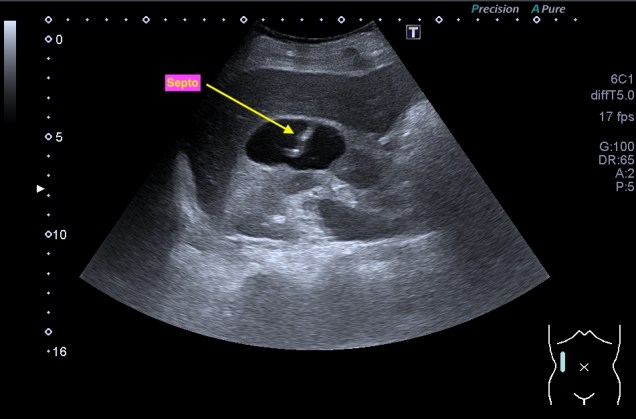

Quiste con septo fino en su interior que en la imagen siguiente comparte espacio con otro septo más grueso que lo clasifica en un nivel superior.

Categoría 2F: Es un quiste simple benigno en un 95% de los casos.

1. Mayor número de septos.

2. Mínimo engrosamiento del septo o calcios groseros o nodulares.

3. Mayores de 3cm.

4. Controles cada 6 meses.